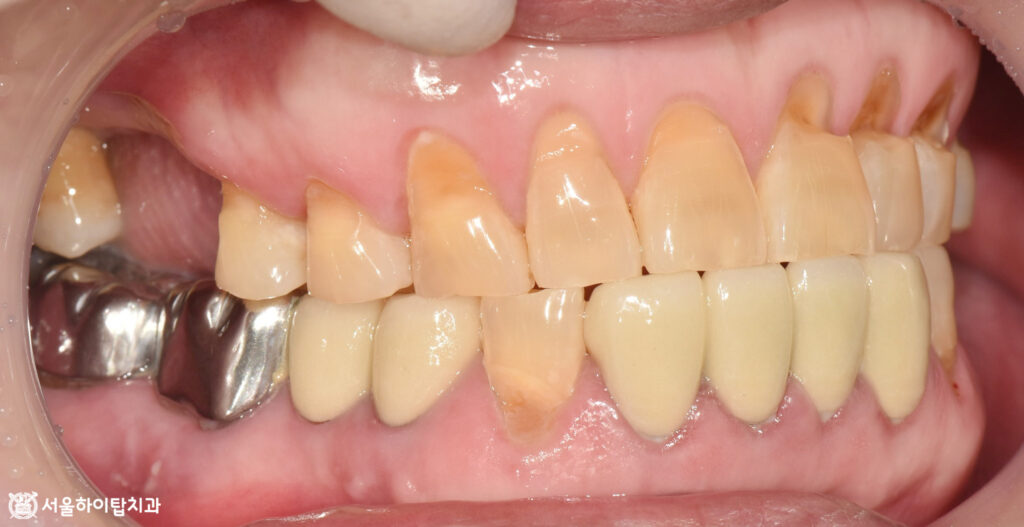

이어서 위에서 바라본 교합면을 살펴보면,

부평 치과 에서는 기존 보철치료가 완료된 아래턱 앞니를 제외하고,

위턱 앞니에서 진행 중인 마모를 뚜렷하게 확인할 수 있습니다.

또한, 뿌리만 남은 치아에서 충치가 진행 중임을 볼 수 있는데,

이는 잔존치근 상태에서 흔히 나타나는 소견입니다.

치관이 없어 청결 유지가 어렵고, 치근 부위에 세균이 쉽게 들어가

치근 우식, 염증, 주변 치조골 흡수를 유발할 수 있습니다.

정면에서 본 모습에서도 문제는 크게 달라지지 않습니다.

전반적으로 구강 내 잇몸 상태가 양호하지 않기 때문에,

균등한 저작 환경을 만들어 저작력 분산과 교합 안정을 확보하는 것이 필요합니다.